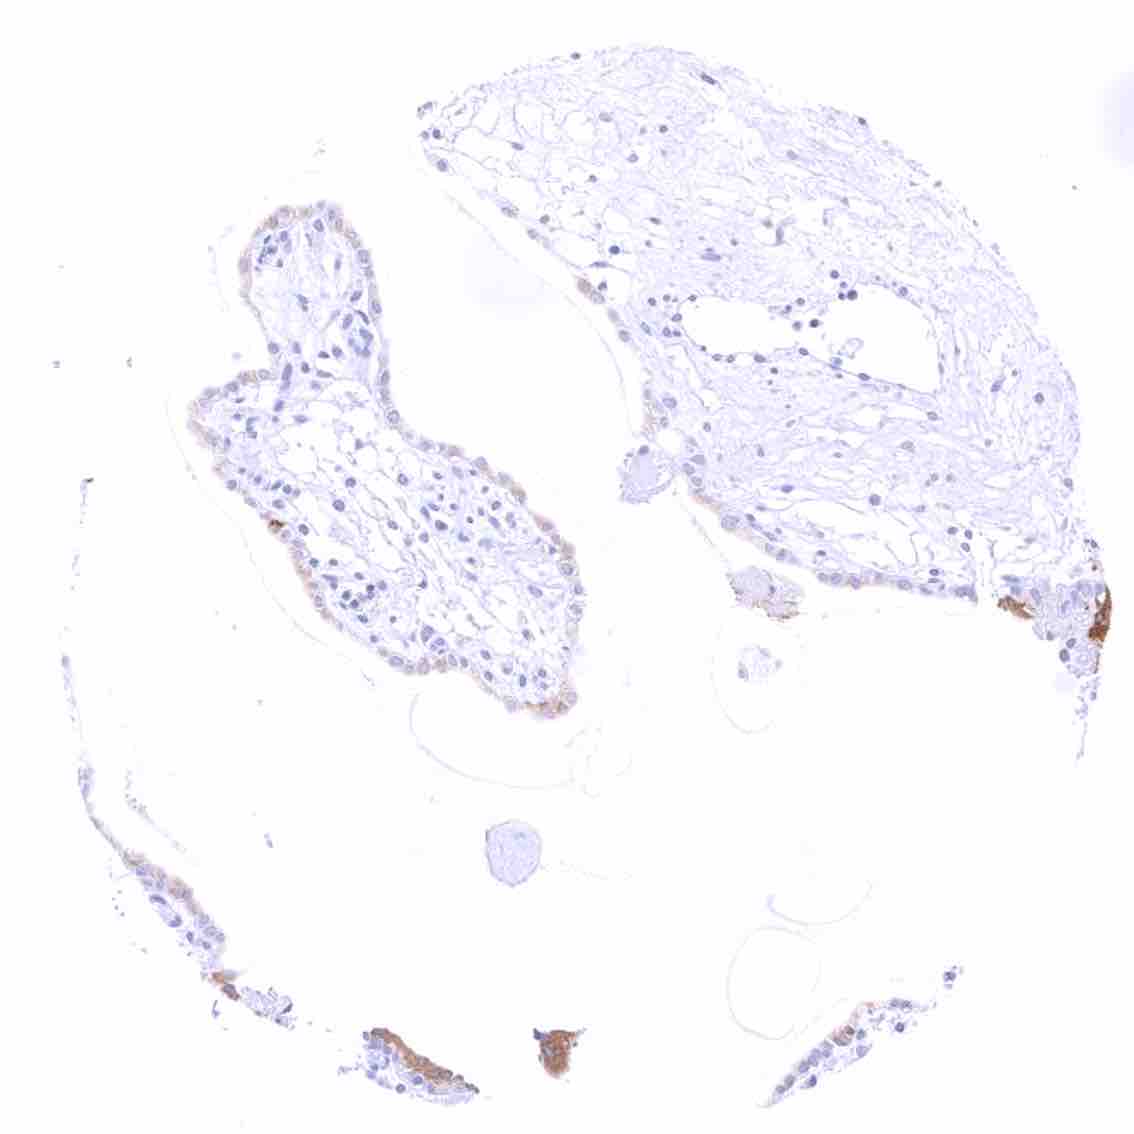

Breast – Distinct cytoplasmic bcl-2 staining of epithelial cells with higher intensity in acinar than in myoepithelial cells.